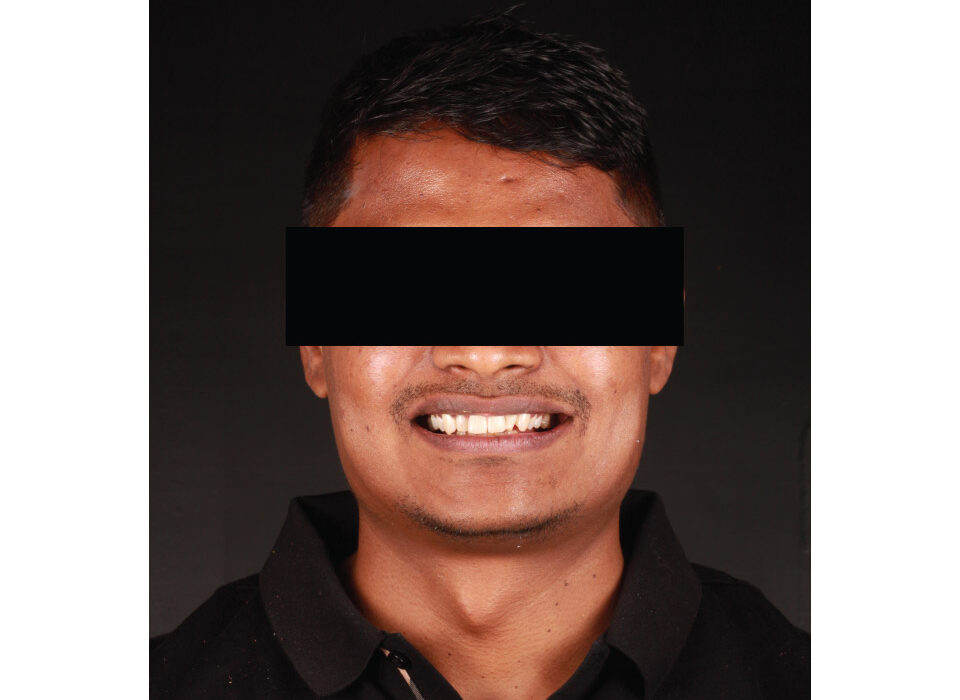

Smile Designing

Highly Advanced & Biocompatible Lithium Di Silicate glass ceramic ingots for life like restorations for enhanced translucency – synergizing aesthetics and function.